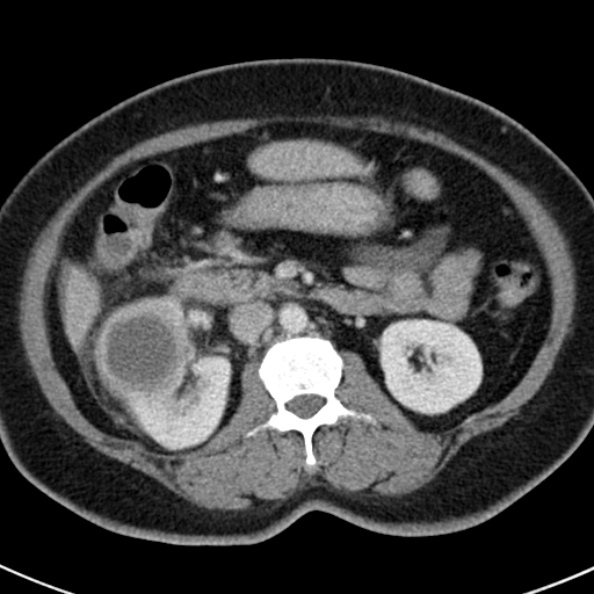

This picture shows the “Ball on tree” appearance of Medullary type RPN

https://www.ctisus.com/responsive/learning/exhibit/genitourinary/311982